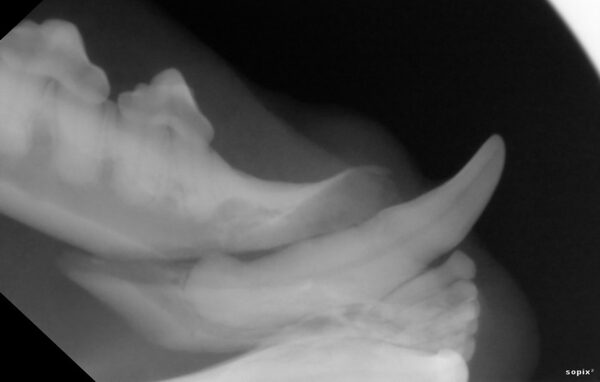

Das wahre Ausmaß zeigte sich allerdings erst nach ausführlicher Untersuchung in Narkose. Das Dentalröntgen und die Sondierung zeigten, dass bereits große Teile des Kieferknochens durch die Parodontitis verursachenden Bakterien zerstört wurde (die gelbe Linie zeigt an, wo der Kieferknochen sien sollte, die rote zeigt an wieviel Knochen bereits zerstört wurde). Dieser Knochenschwund ist leider irreversibel und in diesem Endstadium hilft nur noch die Extraktion.